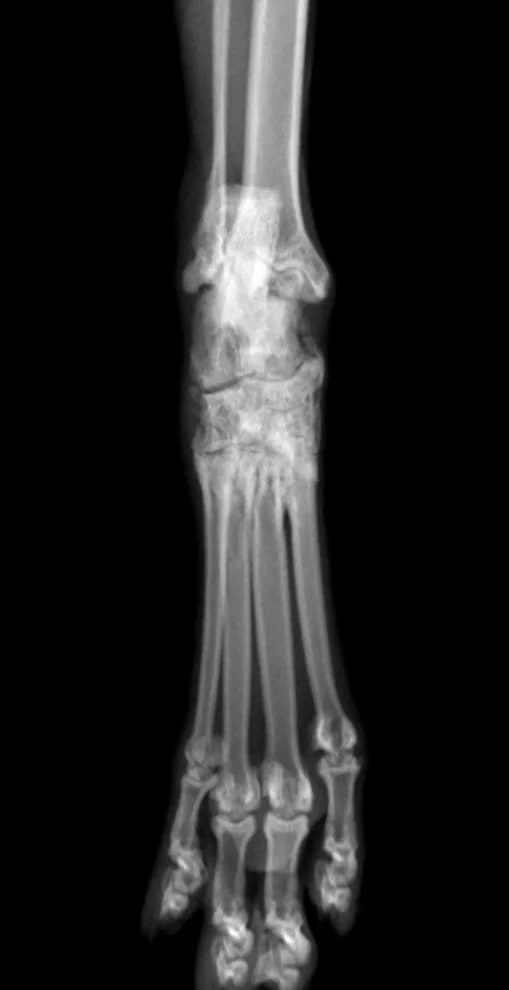

Orthopedic radiographs and genetic testing was performed with sedated patient, which confirmed diagnosis of Osteochondrodiplasia.

radiological finding consisted in irregularity in shape of tarsal and metatarsal bones, narrow tarsal joint spaces, and mild new bone formation around tarsal joints.